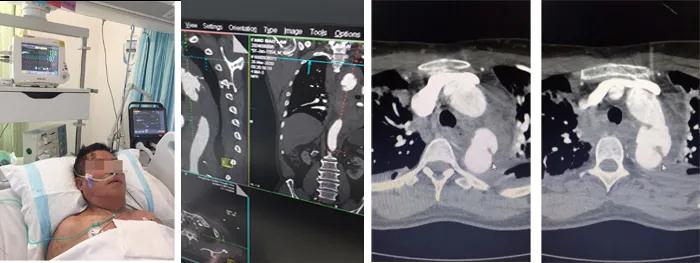

3月26日,66歲的房先生因?yàn)檐嚨準(zhǔn)鹿蕦?dǎo)致全身多發(fā)骨折,生命體征不穩(wěn)定,在當(dāng)?shù)蒯t(yī)院診斷為多發(fā)肋骨骨折、雙肺挫傷、左側(cè)血胸、創(chuàng)傷性失血性休克,CT影像檢查發(fā)現(xiàn)可疑主動(dòng)脈夾層。因病情嚴(yán)重緊急,迅速轉(zhuǎn)運(yùn)至我院急診科,經(jīng)創(chuàng)傷救治綠色通道CT室急診行主動(dòng)脈CTA檢查,示降主動(dòng)脈夾層破裂,縱膈及左側(cè)胸腔大量積血,右側(cè)血?dú)庑亍<痹\收入我院心臟大血管外科。

入院后,患者呼吸微弱,血壓僅65/40mmHg,血常規(guī)示:血紅蛋白由130下降至49g/L。主動(dòng)脈CTA確診患者為主動(dòng)脈夾層破裂,主動(dòng)脈內(nèi)膜撕裂形成假性動(dòng)脈瘤,胸腔和縱膈出現(xiàn)大量積血。柴召?gòu)?qiáng)醫(yī)師考慮患者病情患者危重,休克狀態(tài),隨時(shí)有死亡可能。向醫(yī)務(wù)部周永勤主任匯報(bào),并向患者家屬講明病情,決定急診行主動(dòng)脈腔內(nèi)覆膜支架植入腔內(nèi)修復(fù)術(shù)。